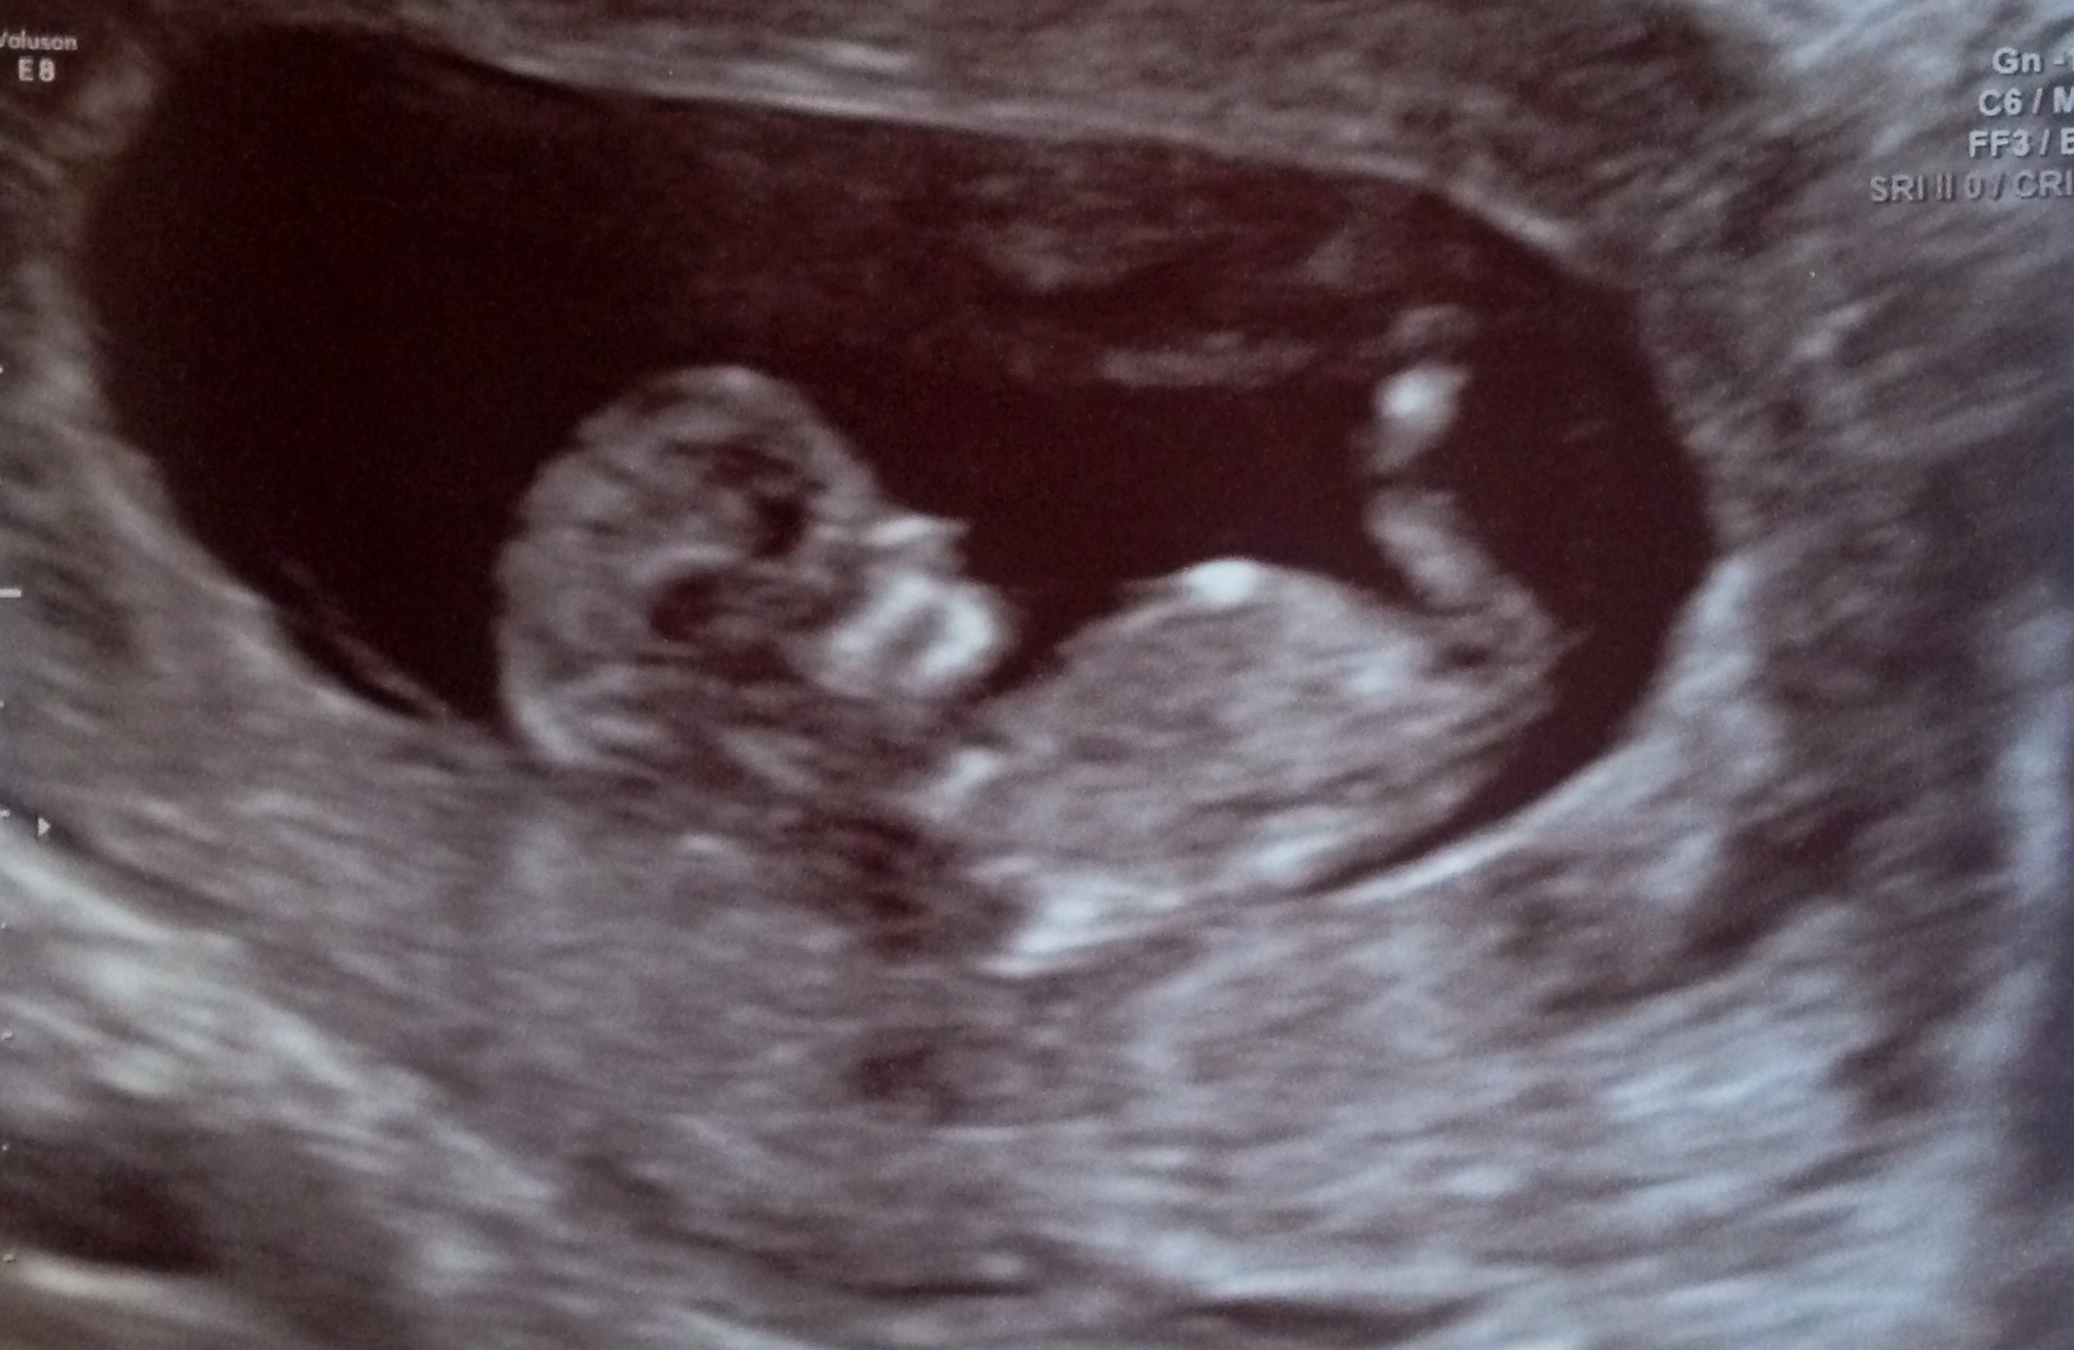

What do you think? 12 weeks 0 days. Thank you!

Tentative boy guess.

i think boy as well :)